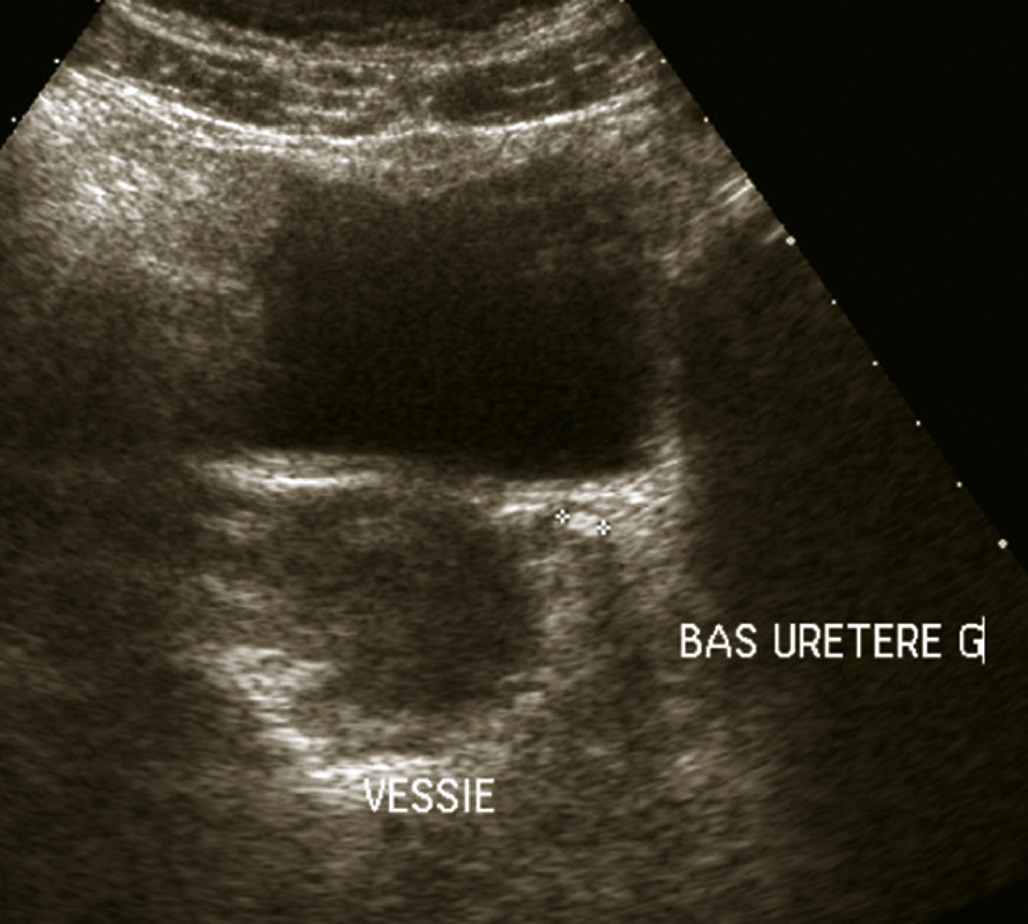

L’échographie abdominale a l’inconvénient d’être opérateur-­dépendante. Ses principales indications sont la lithiase biliaire et ses complications, des douleurs abdominales chez les patients minces et surtout chez la femme pour rechercher une pathologie gynécologique en utilisant le cas échéant des sondes endocavitaires. Ainsi, l’échographie est utile pour affirmer la lithiase biliaire et la cholécystite aiguë (fig. 1) ou objectiver une dilatation de la voie biliaire principale (VBP), rechercher une urétéro-hydronéphrose et des signes indirects en cas de colique néphrétique (fig. 2 et 3), débrouiller le diagnostic des douleurs abdomino-­pelviennes chez la femme.

Colique néphrétique

L’échographie peut montrer une discrète asymétrie des cavités excrétrices rénales, voire l’obstacle lithiasique avec dilatation d’amont (fig. 2 et 3). L’uroscanner complète le bilan et localise si besoin le calcul. Outre le traitement de la cause (calcul, compression extrinsèque…), le traitement antalgique est primordial : anti-inflammatoires non stéroïdiens (AINS), paracétamol, anti­spasmodiques voire dérivés morphiniques. On procédera à la pose d’une sonde urétérale en cas d’anurie (rein unique), de fièvre sur rétention du haut appareil ou de crise hyperalgique.